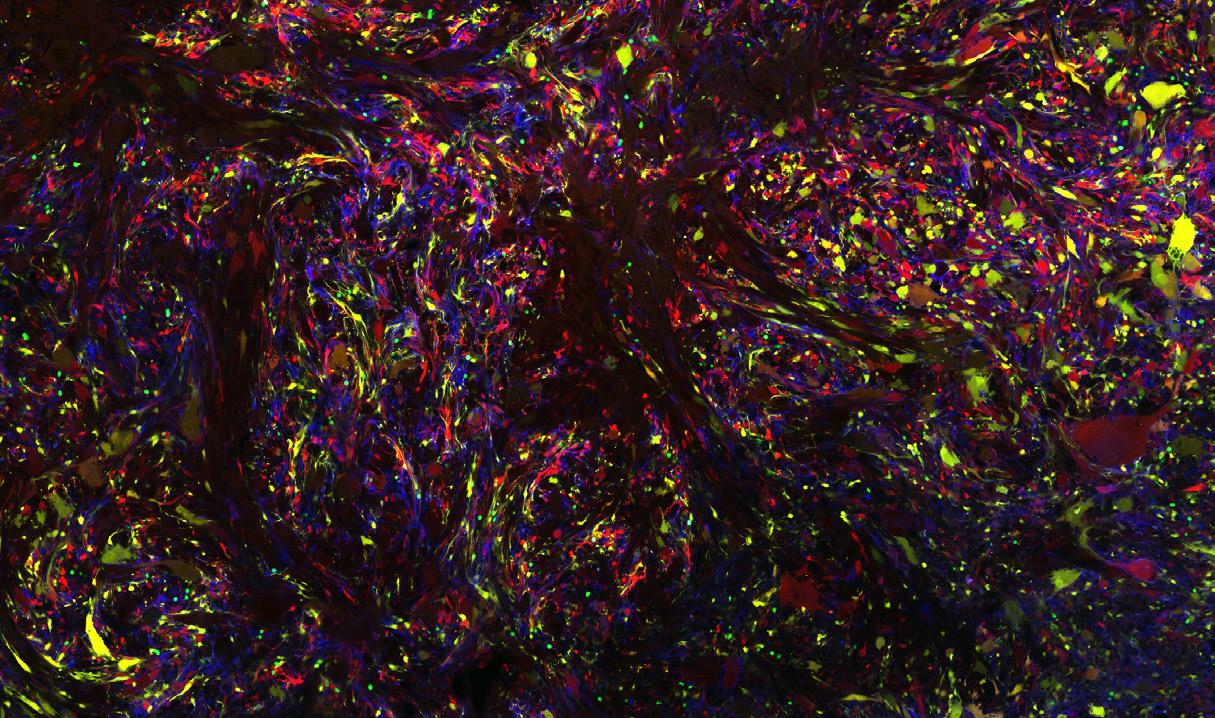

The advanced sequencing technology utilized in the Brain Tumor Microenvironment Laboratory has uncovered the highly variable microscopic genetic features of brain tumors, providing insights into how tumor cells interact with their microenvironment to drive aggressive behavior.

Glioblastoma is an incurable brain cancer. The diversity of glioblastoma cells, illustrated as rainbow colored cells in these images, is a major impediment for successful therapy. By using sc-RNA-seq, a new way of measuring the cells, we found that the diverse malignant cells converge to a limited set of four cellular states. My current goal is to make glioblastoma cells homogenous to develop effective therapy.